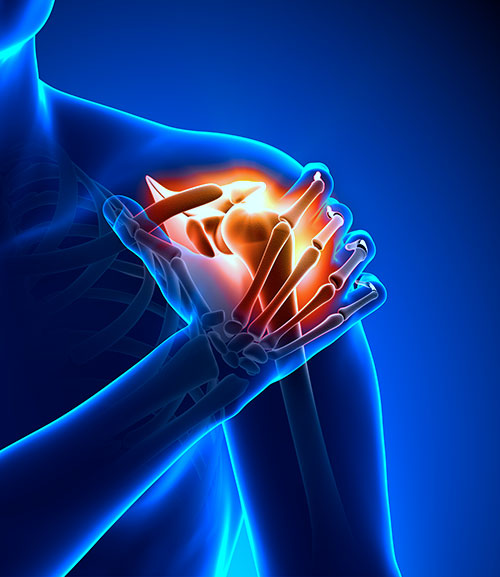

- Joint problems, such as arthritis.

- Overstretched muscles or injuries to muscles, ligaments, and tendons (strains and sprains).

Pregnant women should not use magnetic field therapy, because the safety of this therapy is not proved. People who have medical devices or implants with a magnetic field, such as a pacemaker, should not use magnet therapy, because it could interfere with the function of the implant.

1. When a magnet is applied to the human body, magnetic waves pass through the tissues and secondary currents are induced. When these currents clash with magnetic waves, they produce impacting heats on the electrons in the body cells. The impacting heats are very effective to reduce pains and swellings in the muscles, etc.

9. Magnets have exceptional curative effects on certain complaints like toothache, stiffness of shoulders and other joints, pains and swellings, cervical sponcylitis, eczema, asthma as well as on chilblains, injuries and wounds.